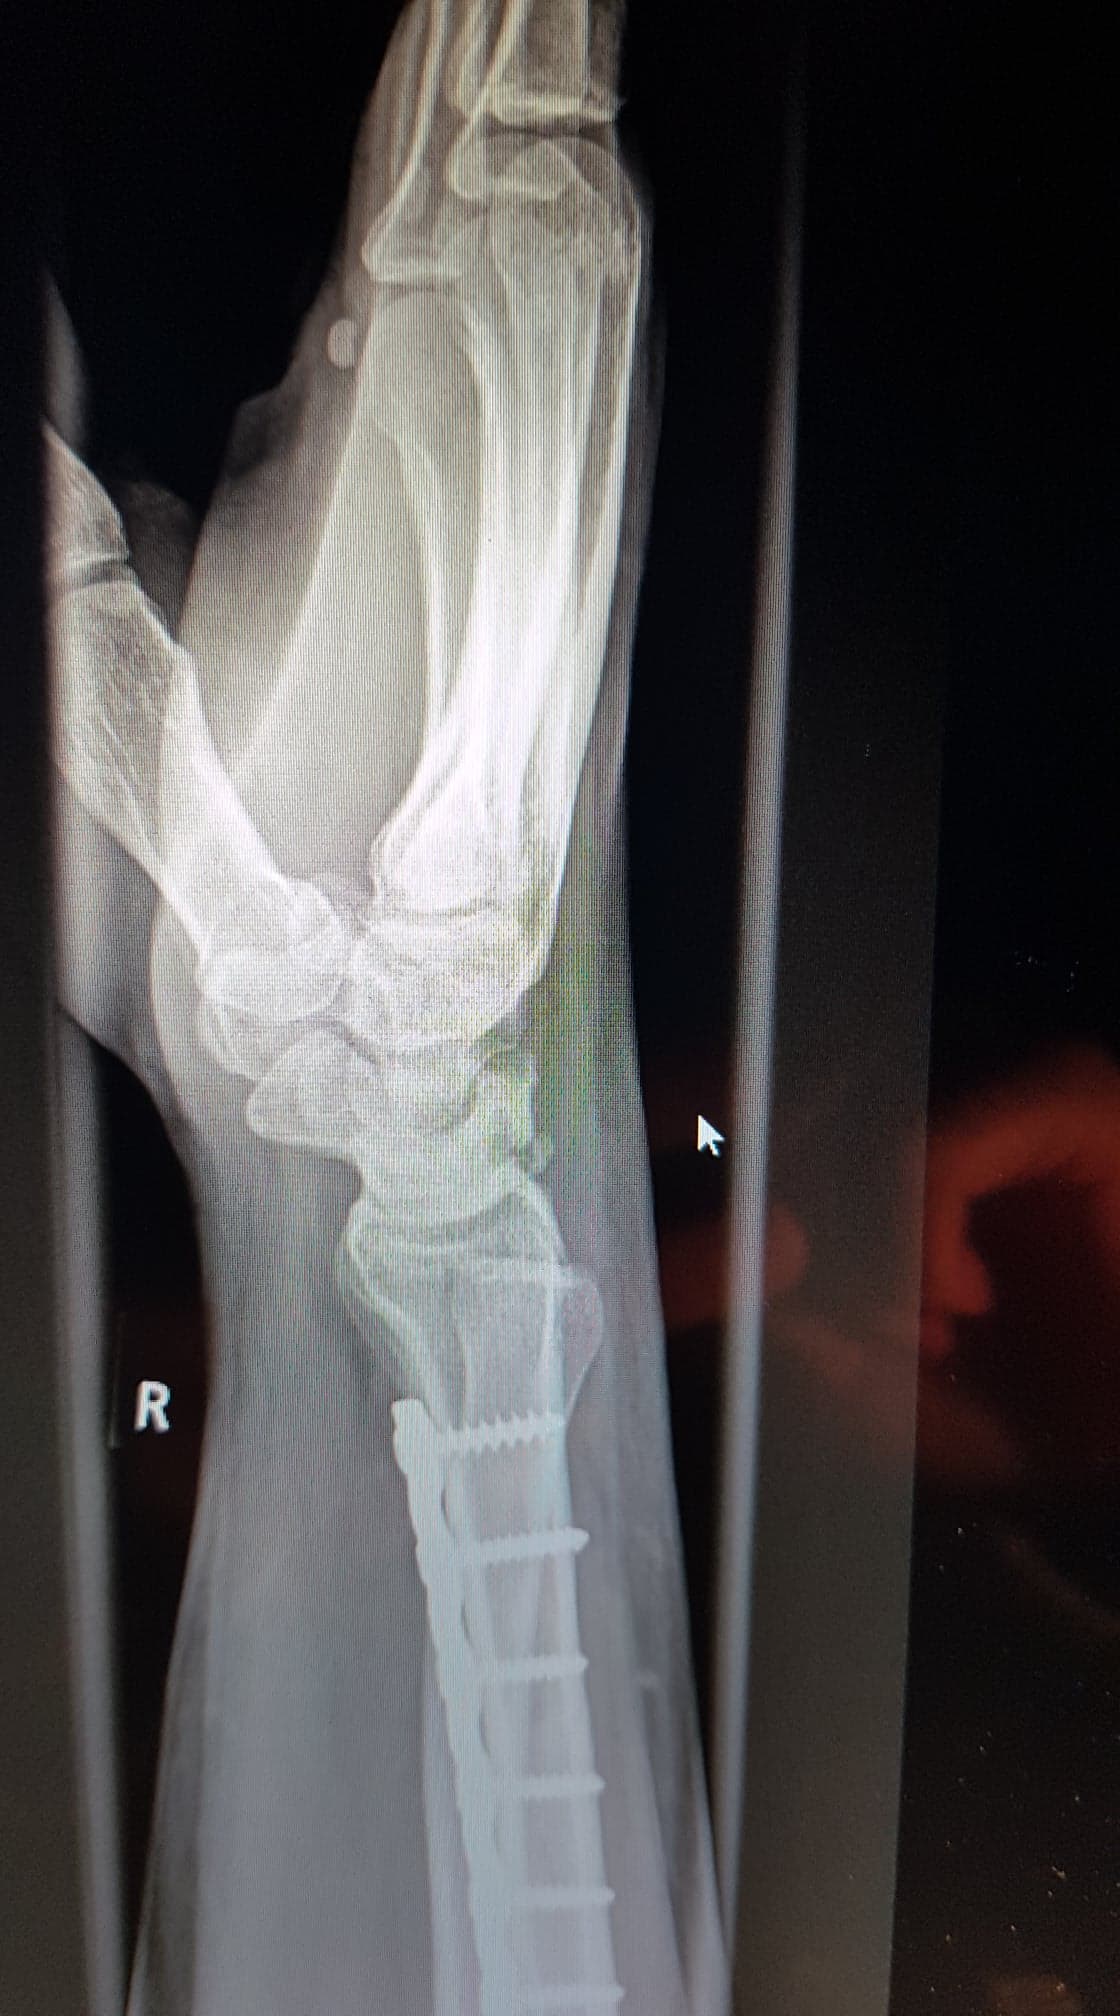

07.07.2017 die erste OP. Radiusverkürzung mit Arthroskopie und Denervierung der Schmerznerven. 2 Tage später durfte ich das Krankenhaus wieder verlassen. Die Narbe sah super aus und die Drenage hat nicht viel Wundflüssigkeit hergegeben. (Homöopathie: Die einen glauben dran, die anderen nicht. Ich habe Sie auf Empfehlung genommen und es hat eindeutig nicht geschadet. Und wenn es nur für den Kopf war, mir tat es gut).

Temporäre ST Transfixation.

Dies war ein kleiner Eingriff, der in der Tagesklinik gemacht wurde. 13.12.2017.

Mit der ST Transfixation bin ich super zurecht gekommen, das Problem war nur, ich durfte die Hand nicht belasten. Also haben wir uns dazu entschlossen die STT Arthrodese (Teilversteifung) zu machen. 27.04.18 Dazu kann ich momentan noch kein Ergebnis geben.